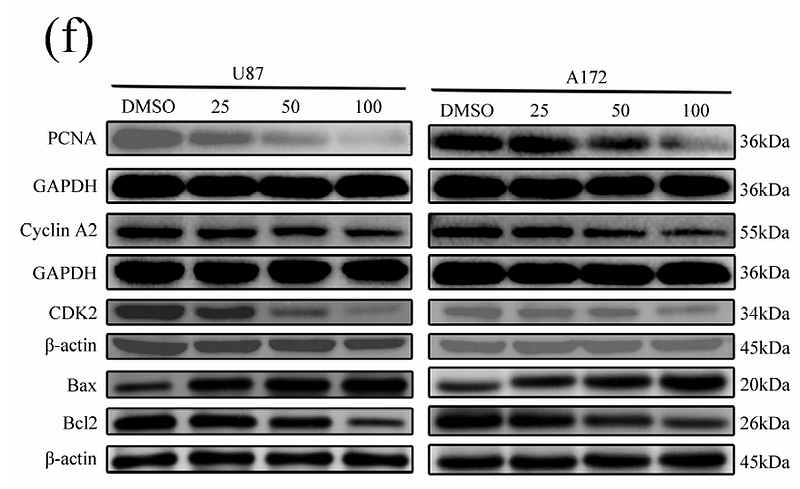

Huafengdan Inhibits Glioblastoma Cell Growth and Mobility by Acting on PLAU and CAV1 Targets

Author: Dengxiao Lin, Wenfeng Yu, Jia Yu, Sha Cheng, Yu Song, Xiaoqing Wan, Yingjiang Xu, Heng Luo, Baofei Sun

PMID: 40143204

期刊: Pharmaceuticals

应用: WB

反应种属: Human

发表时间: 2025 Mar

Betulinic Acid Inhibits Glioma Progression by Inducing Ferroptosis Through the PI3K/Akt and NRF2/HO-1 Pathways

Author: Jinxiang Huang, Qixuan Li, Hongxiang Wang, Shuai Zhang, Xiaorong Zhou, Fang Huang, Juxiang Chen, Luning Xu, Dezhi Kang

PMID: 39965807

期刊: Journal Of Gene Medicine

应用: WB

反应种属: Human

发表时间: 2025 Feb